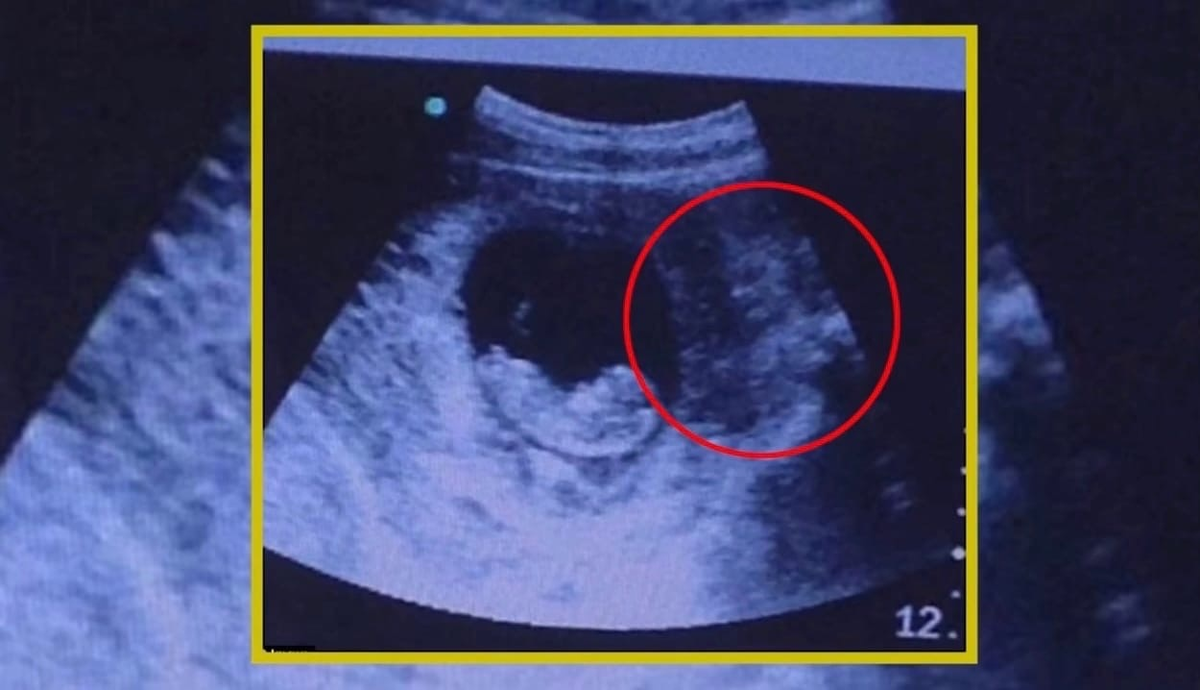

Ультразвуковое исследование (УЗИ) на неделе может быть очень важным моментом для будущих родителей. Ведь это их первая возможность увидеть своего малыша на экране и получить представление о его развитии. Однако, мало кто знает, что во время УЗИ малыш может проявлять свои эмоции, как и во время обычной жизни в утробе мамы.

Что же делает малыш, когда проводят УЗИ? Он может смеяться и плакать, хотя не испытывает этих чувств в полном смысле слова. Когда малыш смеется, его лицевые мышцы могут подергиваться, а головка немного колышется. А когда он плачет, можно увидеть, как маленькие кулачки и ножки двигаются ритмично и энергично.

Кроме того, во время УЗИ малыш может делать много других интересных вещей. Он может вытягивать руки и ноги, крутиться вокруг своей оси и даже попытаться заглотить свой пуповинный шнурок. Иногда малыш может запрыгнуть и прыгнуть, показывая свою активность и жизнерадостность.

Малыш на ультразвуковом исследовании может даже смеяться! Несмотря на то, что ему всего несколько недель, он уже способен проявлять свои эмоции и радоваться. Когда родители смотрят на экран, они могут увидеть, как малыш шевелится, делает забавные движения и улыбается. Это очень замечательный момент для будущих родителей, который создает особую связь с малышом уже до его рождения.